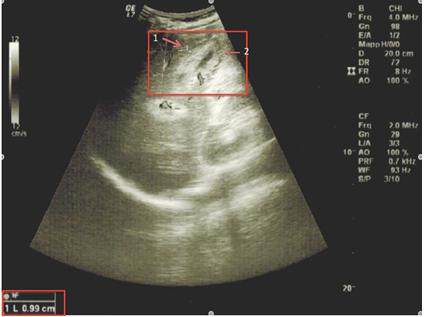

患者每天服用多西环素200 mg和利福霉素15 mg/kg/d治疗6周,未接受胆囊切除术。患者的发热、腹痛逐渐消失,肝功能恢复正常。服用抗生素2周后复查腹部超声示胆囊体积、胆囊壁均未见异常,腹腔积液消失。